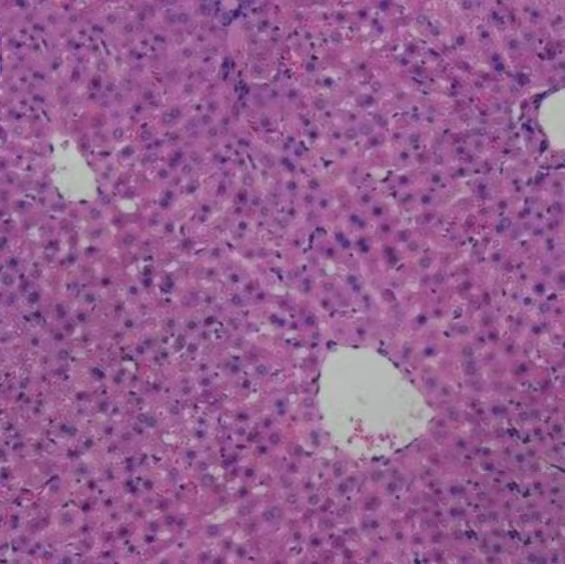

3.在预定时间点处死大鼠,采集肾脏样本,进行组织病理学检查,包括HE染色和Masson染色,以观察肾小球硬化、肾小管萎缩、肾间质纤维化和炎性细胞浸润等病理变化。